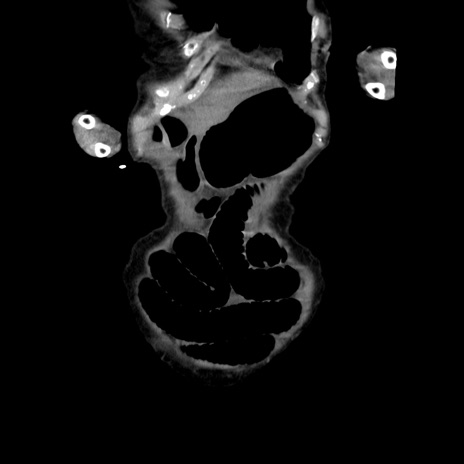

横断像

【症例】80歳代女性

【主訴】嘔吐、腹痛

【現病歴】数時間前より嘔吐あり。心窩部痛出現し、徐々に右下腹痛あり。その後も数回嘔吐あり救急搬送となる。

【既往歴】左大腿骨頚部骨折手術

【身体所見】腹部は膨隆しているが軟らかく圧痛なし。腸雑音はやや亢進。

【データ】WBC 12000、CRP 19.05